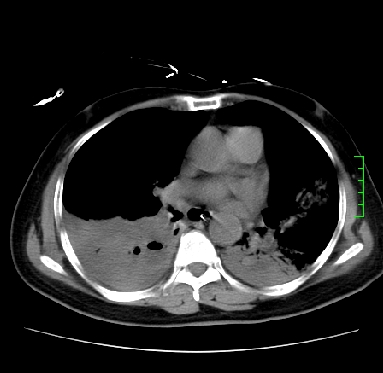

icu病人,几天都没明确诊断。m,76y,咳嗽、咳痰1周,伴气促,右胸痛入院,pe:t38.3c p135 r25 bp135/85。双肺可闻及大量湿罗音,心、腹未见明显异常。诊断:1心衰?2肺部感染?3冠心病?

11号ct

1)两肺感染性病变(右肺下叶肺脓肿可能)。2)双侧胸腔积液,以右侧为甚。

ards,肺感染性病变,右下叶实变,双侧胸腔积液,右侧为著,叶间胸膜积液,右上肺陈旧性tb纤维灶,左室大。

考虑:双肺感染、右肺下叶肺脓肿,双侧胸腔积液,肺水肿.请结合临床.